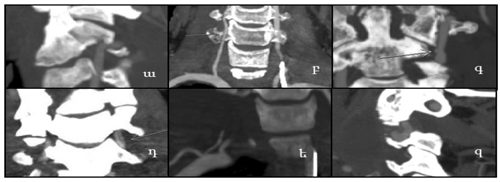

Ընդհանուր առմամբ ԿՏԱ տվյալներով հայտնաբերվել են պարանոցային զարկերակների 43 վնասվածքներ, որը կազմում է ընդհանուր հիվանդների թվի 30.3%-ը: Հայտնաբերվել են ՊԶՎ-երի վնասվածքների հետևյալ տարատեսակները. անոթի ճնշում (ո=3, 7.0%) (նկ.1-ա), սպազմ (ո=4, 9.3%) (նկ.1-բ), ինտիմայի թեթև վնասվածք (ո=7, 16.3%) (նկ.1-գ), անոթի շերտազատում (ո=12, 27.9%) (նկ.1-դ), անոթի խցանում (ո=15, 34.9%) (նկ.1-ե)

և կեղծ անևրիզմա (ո=2, 4.7%) (նկ.1-զ):

Նկար 1. Ողնաշարի պարանոցային հատվածի կոմպյուտերային տոմոգրաֆիկ անգիոգրաֆիայի արդյունքում հայտնաբերված՝ա) անոթի ճնշում, բ) սպազմ, գ) ինտիմայի թեթե վնասվածք, դ) շերտազատում, ե) խցանում, զ) կեղծ աներիզմա